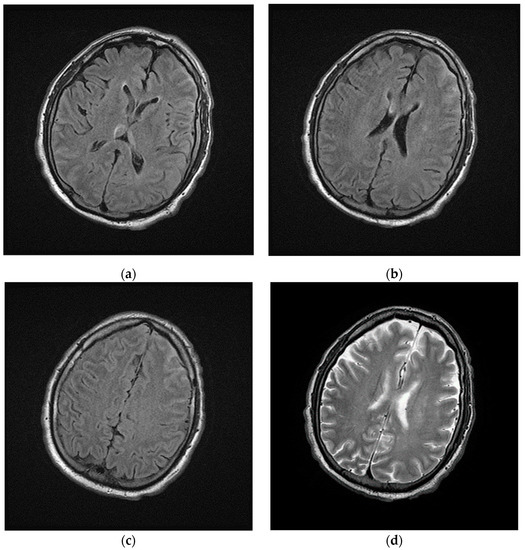

2.1. Hospital Phase

2.2. Post Hospital Phase